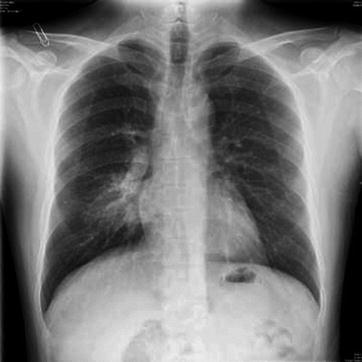

X-ray demonstrates increased, thickened, blurry, and deranged pulmonary markings, which are especially obvious at the middle and medial parts of the both middle and lower lungs. The transparency of lung fields is increased, with pulmonary emphysema as well as enlarged and thickened hilar shadow (Figs. 23.9, 23.10, 23.11, and 23.12). The severe cases are often characterized by flakes of consolidation shadows and extensive exudative lesions in the lungs. The conditions are possibly complicated by pleural effusion and pneumothorax (Figs. 23.13, 23.14, 23.15, 23.16, and 23.17).

Pediatric measles complicated by pneumonia. (a) X-ray demonstrates enhanced and blurry pulmonary markings in both lungs and patches of shadows in both lungs, especially in the right lung. (b) By reexamination after the treatment for 4 days, the lesions are demonstrated to be absorbed and improved

Fig. 23.12.

Pediatric measles complicated by pneumonia. (a) X-ray demonstrates enhanced pulmonary markings in both lungs, flakes, and cotton wool-like shadows at the medial part of the right middle and upper lung fields. (b) By reexamination after treatment for 16 days, the lesions at the lungs are demonstrated to be absorbed and improved